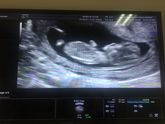

Симфизит ... поздравляю

13 июля 2018 23:11

Все ни как эта беременность не хочет протекать в обычном русле. Поздравляю себя с симфизитом в 9 мм. Скорее всего рожать буду в 5 род доме . Хочу попасть к Нелюбову. Хвалят его. Но думаю поговорить со своим врачем в поликлинике на счёт КС. Все так и … Читать далее